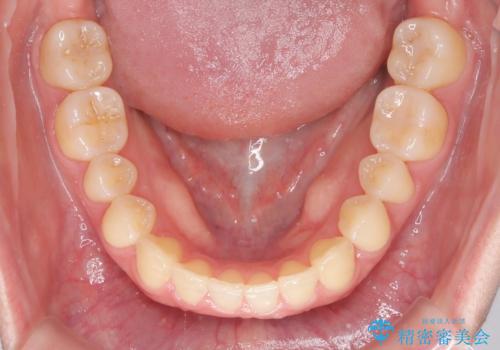

- 前歯のガタツキが気になるとのことで来院されました。

ワイヤー矯正とインビザライン矯正を併用することによって、治療期間の短縮と、より良い仕上がりを目指す治療を選択することとしました。

インビザライン(アライナー)矯正とワイヤー矯正のそれぞれの利点を生かした治療を行い、綺麗な歯並びになりました。